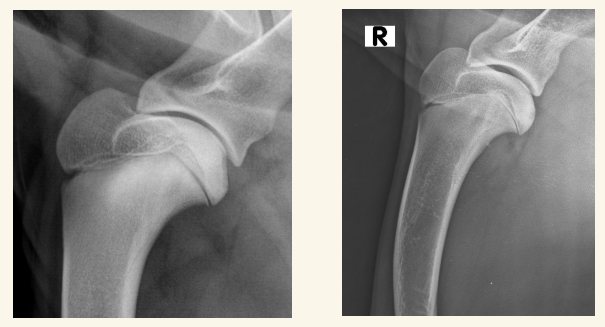

Hombro:

Luxaciones lo mas común (Puede ser congénita y traumática). Puede haber Osteocondritis disecante, Fracturas o EDA (Enfermedad Degenerativa Articular)